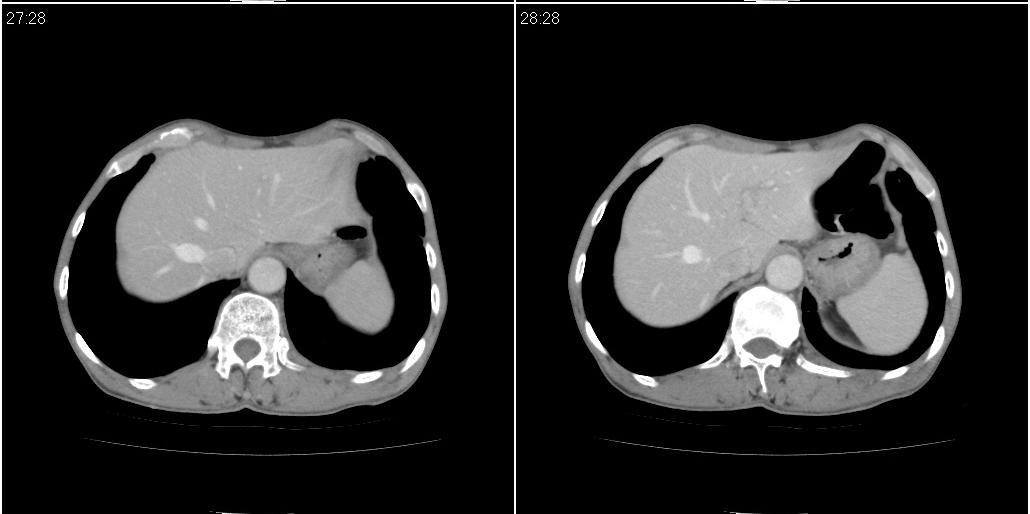

以下是ct检查的情况:

标题: ct增强:

[本贴已被 fanshl 于 2010-3-30 7:14:31 修改过]